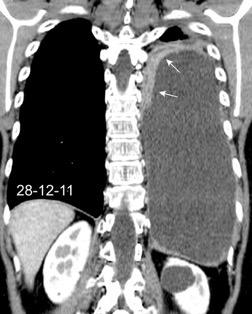

49. INVERSIÓN DIAFRAGMÁTIC. MESOTELIOMA

La ocupación del espacio pleural por derrame (o obstrucción aérea) se acomoda con expansión aumentada de la caja torácica, especialmente en eje vertical. La consecuencia es aplanamiento e incluso inversión diafragmática.

Afzal S, Fatima K, Ambareen M. Antenatal ultrasound diagnosis of congenital high airway obstruction syndrome: a case report and review of literature. Cureus. 2019. Thoma R et al. Physiology of breathlessness associated with pleural effusions. Curr Opin Pulm Med. 2015

Wang JS et al. Changes in pulmonary mechanics and gas exchange after thoracentesis on patients with inversion of a hemidiaphragm secondary to large pleural effusion . Chest 1995

Mesotelioma epitelioide